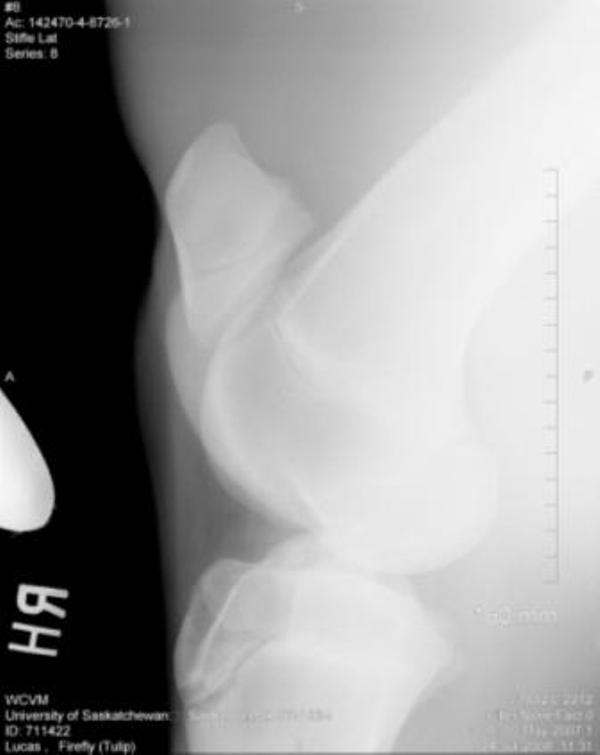

Bilateral Tarsi:

Left Tarsus:

There is a small osseous protrusion off of the distal aspect of the medial trochlear ridge. This is a normal variation. There is also a very small linear osseous fragment visible dorsal to the proximal intertarsal joint in the lateral view This may be a normal finding or it may be a small osseous fragment from more proximity in the tarsus. No Obvious defect or origin of this fragment is noted, however.

Thank you so much for your assistance, it is really appreciated!! I finally have the cd of the x-rays and will be posting them here. Again, thank you!! The first 2 are stifle pictures, the rest are of the hock.

As there were some left hock abnormalities noted, I am now posting her hock pictures.